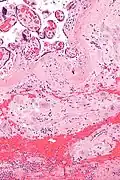

| Micrograph of a chronic deciduitis, showing the characteristic plasma cells. H&E stain. | |

Chronic deciduitis is a type of long-lasting inflammation that arises in pregnancy and affects the endometrial stromal tissue (decidua).

It is associated with preterm labour.[1] The diagnosis rests primarily on the presence of plasma cells.[2]